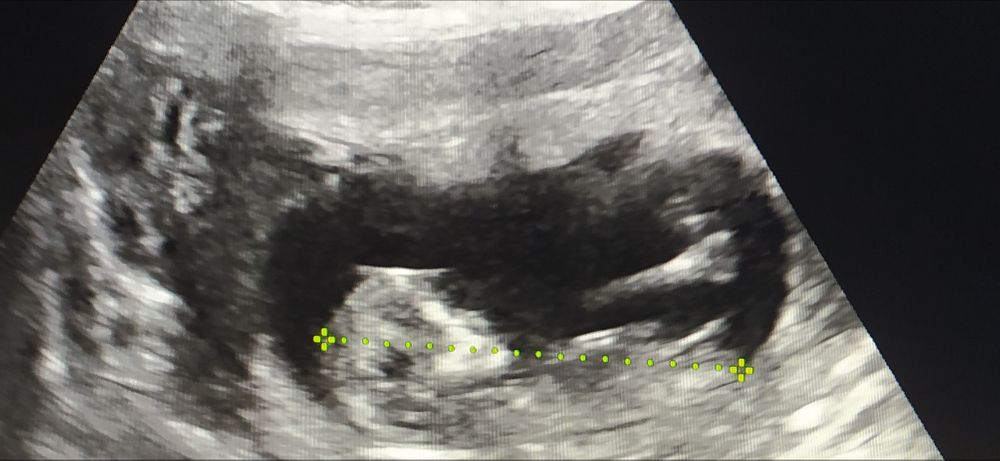

Нам узист объяснила, что сложно точно угадать на таком сроке, но если этот бугорок больше под прямым углом - мальчик, если под наклоном - девочка. В нашем случае торчал, как пистолет, не ошиблась😀 У вас похоже на девочку.

Пока больше похоже на девочку, но еще очень рано. И бугорок немного вздернут вверх вроде, поэтому мальчика тоже не исключаю. В общем, не расстраивайтесь раньше времени🙏

Девочка, почти параллельно с позвоночником

лилия Ахметшина, бугорок параллельно с позвоночником, угол совсем маленький, у мальчиков чуть больше, но мы ведь с вами не спецы